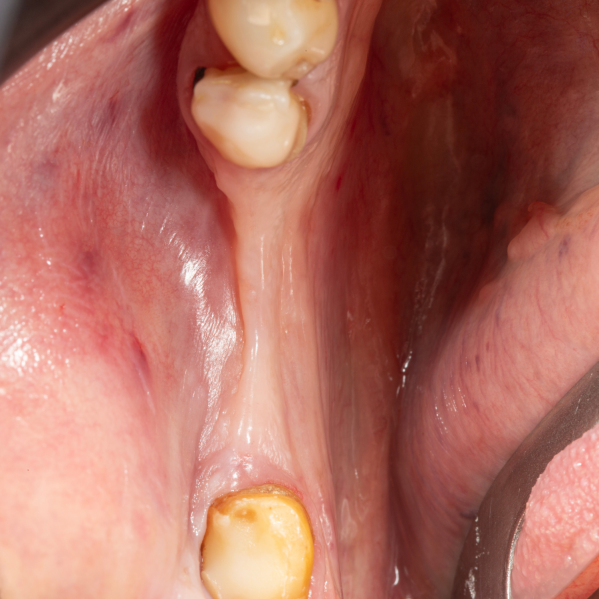

İmplant etrafındaki kemik açıklığını kemik grefti ile tedavi ettiğimiz vakamız.